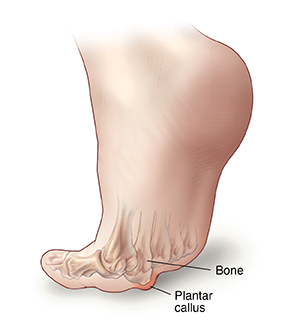

Plantar callus

When one metatarsal bone is longer or lower than the others, it presses on the skin beneath, forming a callus. Wearing shoes with thin soles and high heels can also place extra pressure on the ball of your foot. As a result, the callus may cause foot pain and irritation.